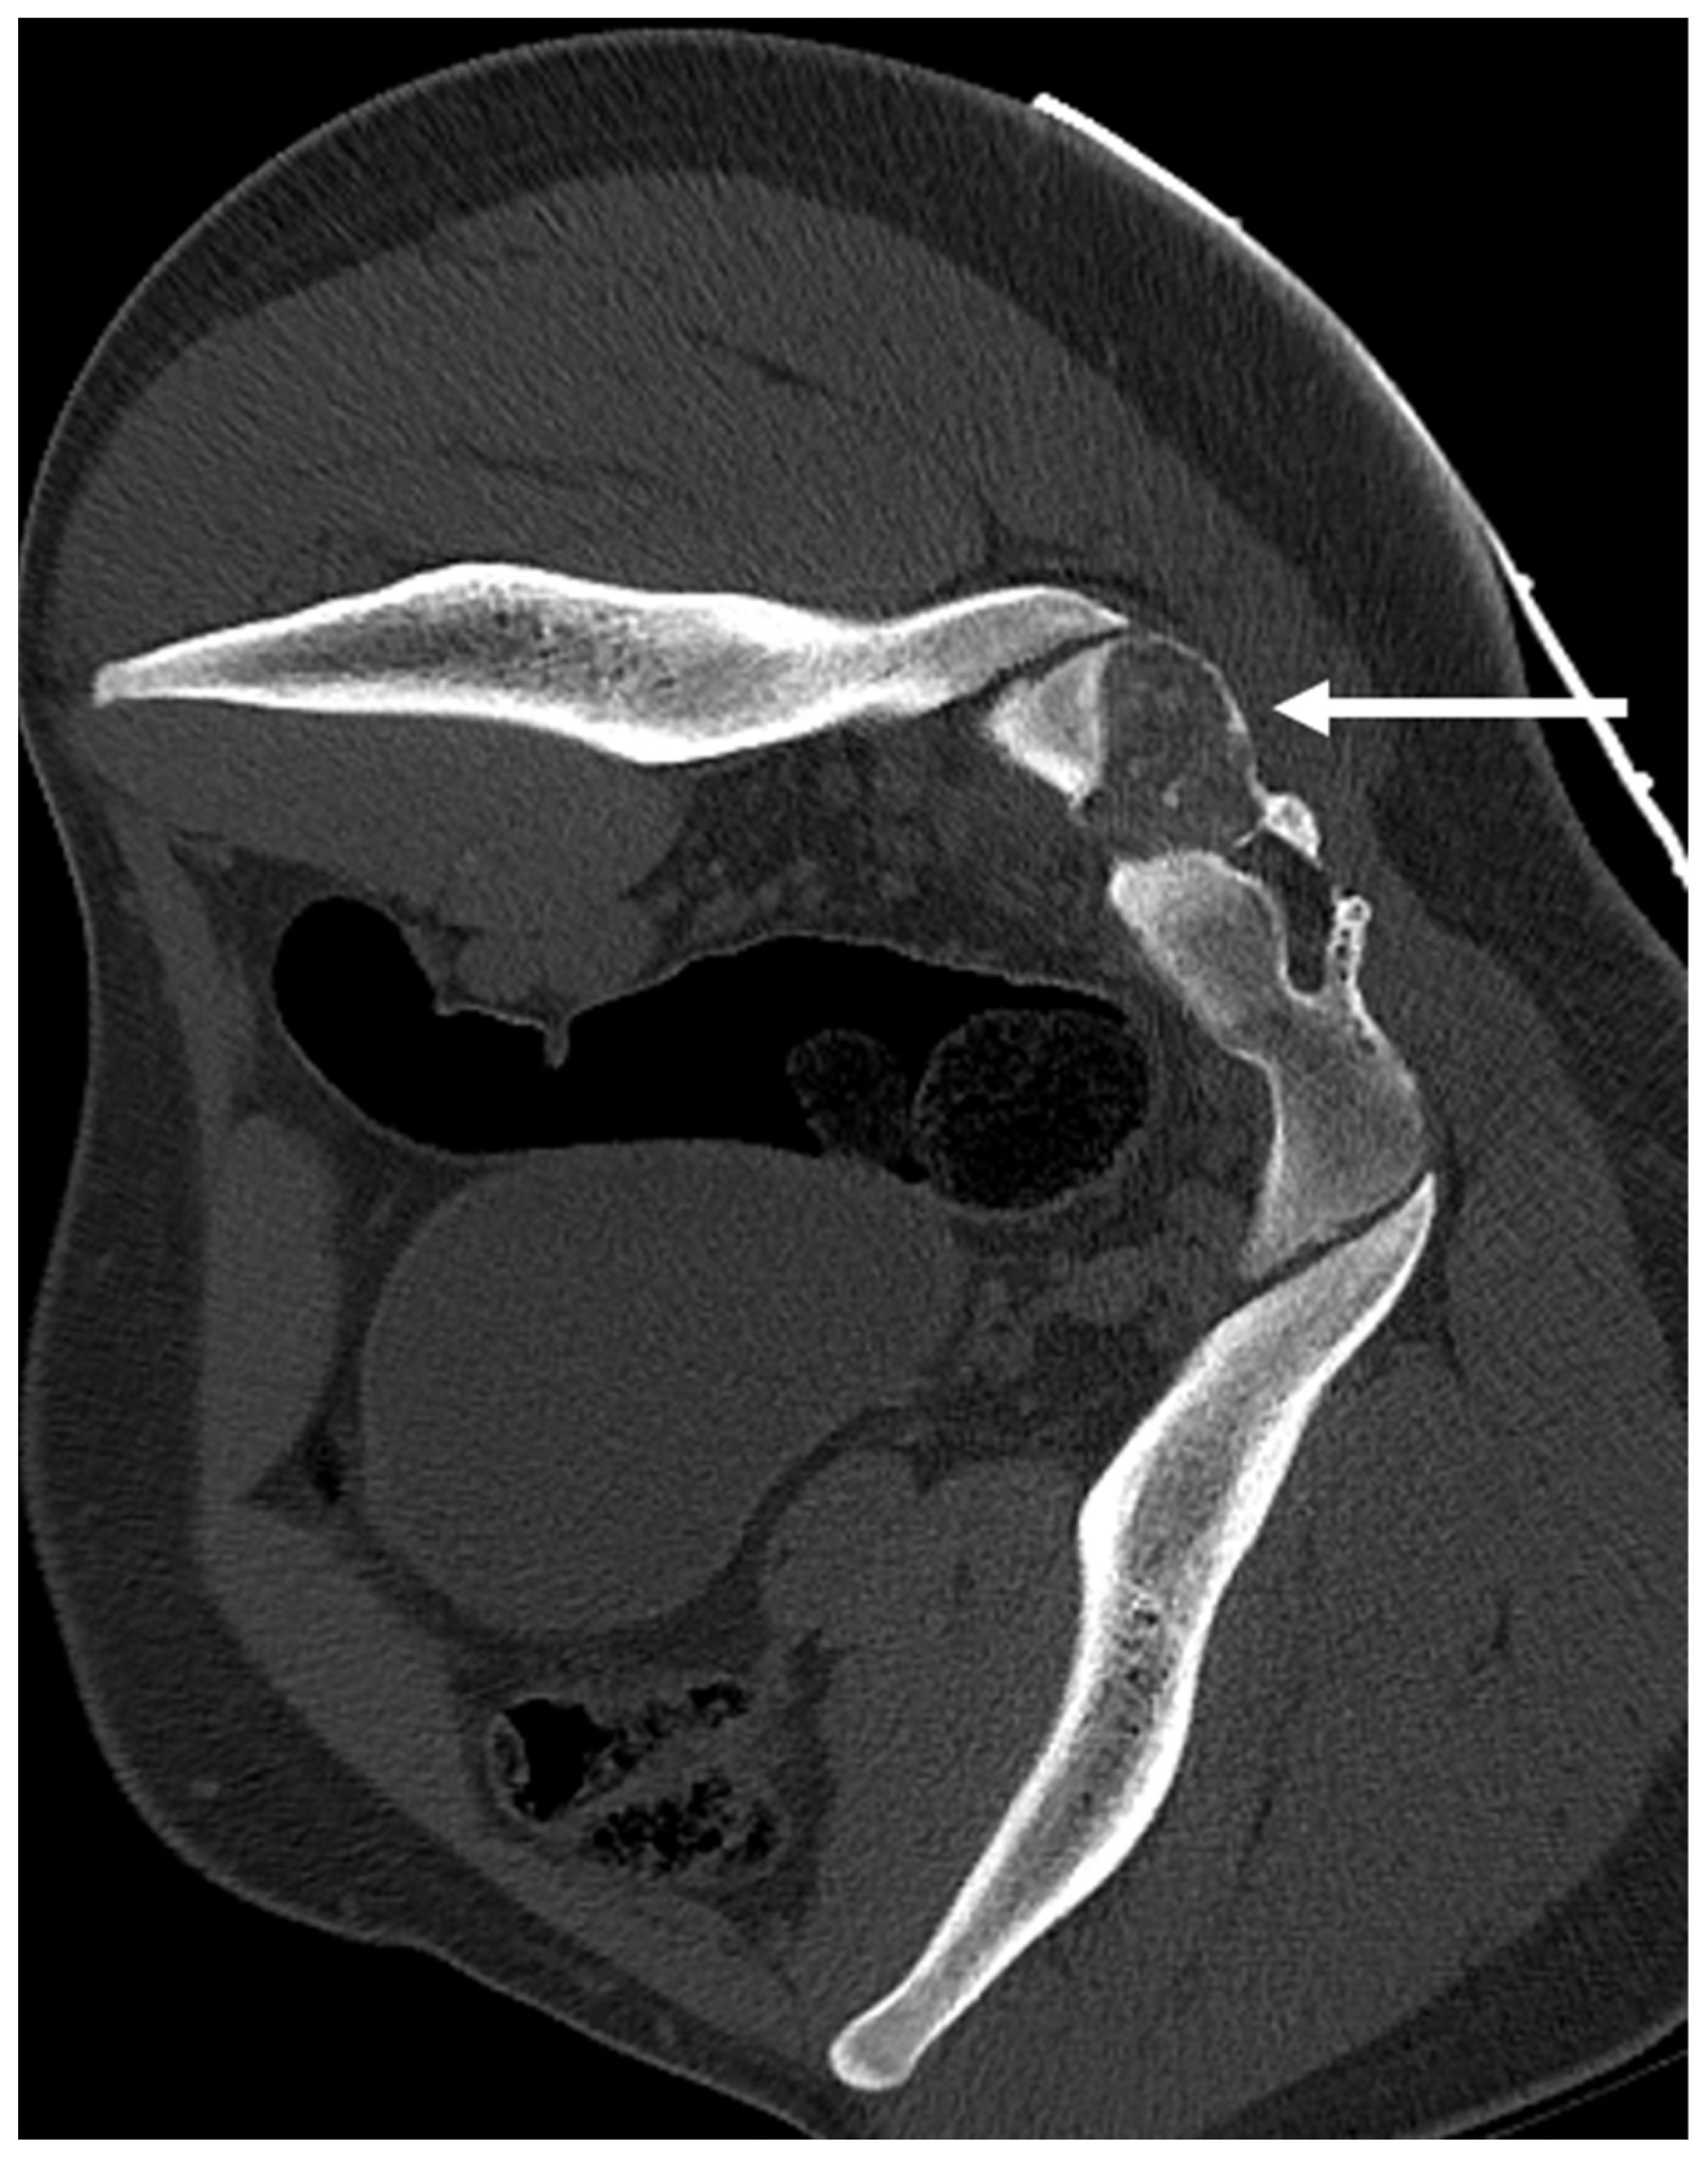

3.6. Chondroblastoma

| Osteochondroma | Lesion continuity with cortex and medulla. | Cartilage cap |

| Chondroblastoma | Osteolytic lesion. Variable intralesional calcification (chondroid matrix) | Extraosseous soft tissue component |